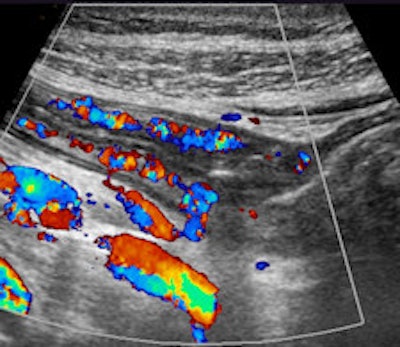

Cross-sectional (left) and longitudinal (right) images of the terminal ileum show thickened bowel wall and inflammatory echogenic fat in a young female patient with acute Crohn's disease of the terminal ileum. All images courtesy of Dr. Stephanie Wilson.

Additional color Doppler images show hyperermia of the bowel.

Additional color Doppler images show hyperermia of the bowel.When performing ultrasound of the gastrointestinal tract, there are technical and patient-related challenges. The technical demands include equipment requirements for a broad range of transducer frequencies to allow for scanning of the bowel within the focal range of the transducer so that exceptionally high resolution can be achieved. Although all ultrasound machines have low-frequency probes available, it is the addition of high-frequency probes, both linear and convex, which allows for good bowel assessment, especially in thin patients.